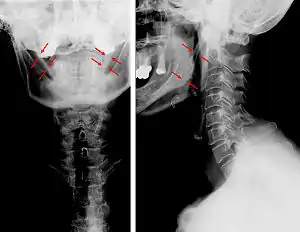

3D-reconstructed CT scan showing bilateral stylohyoid ligament ossification -

3D reconstructed CT scan showing elongated styloid process (right side)

Diagnosis is suspected when a patient presents with the symptoms of the classic form of "Eagle syndrome" e.g. unilateral neck pain, sore throat or tinnitus. Sometimes the tip of the styloid process is palpable in the back of the throat. The diagnosis of the vascular type is more difficult and requires an expert opinion. One should have a high level of suspicion when neurological symptoms occur upon head rotation. Symptoms tend to be worsened on bimanual palpation of the styloid through the tonsillar bed. They may be relieved by infiltration of lidocaine into the tonsillar bed. Because of the proximity of several large vascular structures in this area this procedure should not be considered to be risk free.

Imaging is important and is diagnostic. Visualizing the styloid process on a CT scan with 3D reconstruction is the suggested imaging technique.[11] The enlarged styloid may be visible on an orthopantogram or a lateral soft tissue X ray of the neck.